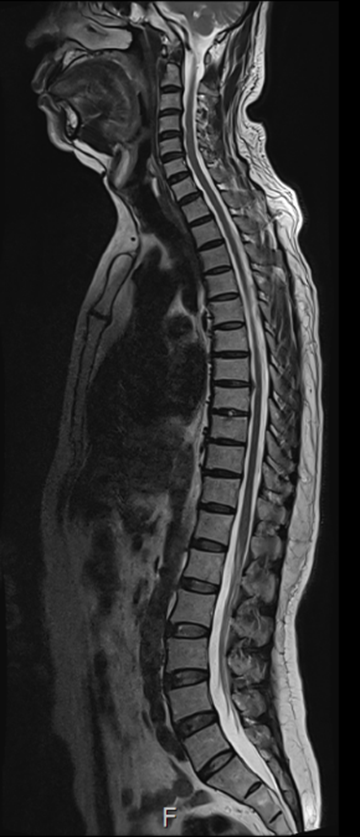

그림9.png 촬영 일시: 2025.02.11

<Fig 1. 경추-흉추-요추의 MRI, 퇴행성 디스크>

✔️ 경추, 흉추, 요추의 퇴행성 디스크

✔️ 요추 5번-천추 1번의 진행 중인 신경근병증

✔️ 경추 5, 6, 7번 신경근병증까지 동반되어 있었습니다